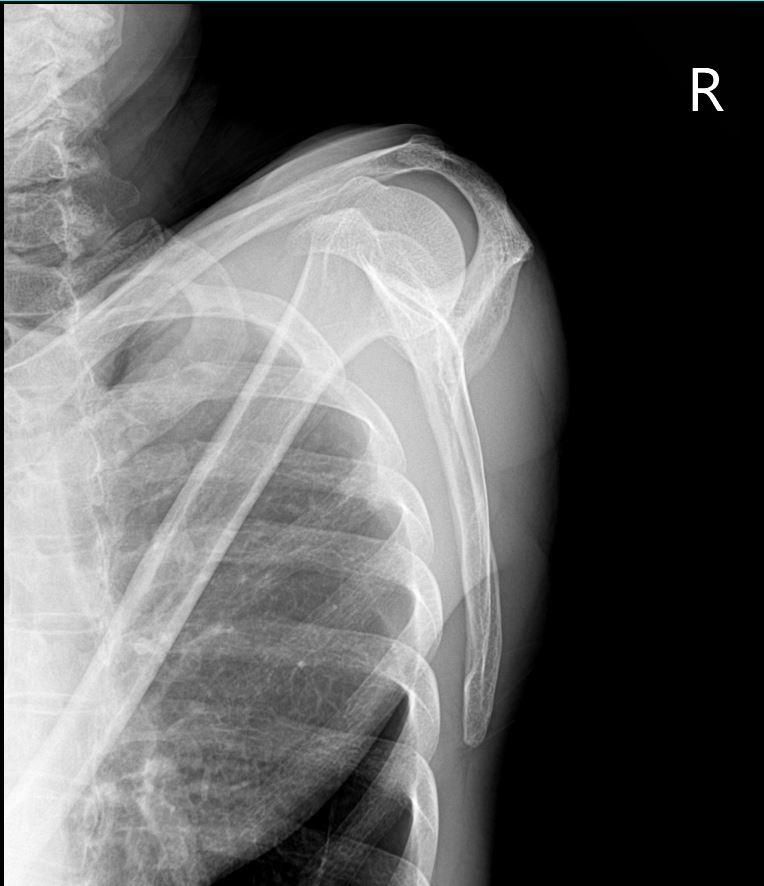

엑스레이 사진상 어깨탈구 소견이 있나요?

하기 사진은 그날 찍은 어깨 엑스레이입니다.

혹시 엑스레이상 어깨 탈골 소견이 있는지 궁금합니다.

업로드 하신 어깨 엑스레이 사진에는 딱히 보이는 이상소견이 따로 있지 않습니다. 어깨 부위 탈구 소견이 관찰되지 않으며 정상 어깨 엑스레이 사진으로 보입니다. 어깨의 탈구가 있으면 심한 통증과 함께 움직임에 제한이 생기므로 단순히 소리가 나는 소견만으로는 탈구에 대해서 크게 걱정을 할 필요는 없습니다.

올려주신 어깨 엑스레이를 보면 뼈구조가 정상적으로 위치하고 있으며 명백한 탈구나 골절 소견은 보이지 않습니다. 어깨 관절은 비교적 안정적인 상태로 보입니다. 다만 어깨에서 뚝소리가 나는 것은 관절이나 힘줄, 인대가 움직이면서 나는 소리일 수 있으며 반드시 탈골을 의미하지는 않습니다! 통증이 없고 움직임도 정상적이라면 큰 문제 가능성은 낮습니다!안녕하세요. 김현태 물리치료사입니다.